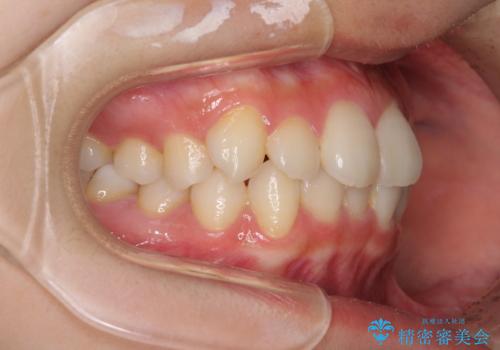

- 前歯のデコボコを気にして来院された患者様です。

叢生と捻転が随所に認められるものの、マウスピースで十分対応可能であったため、インビザラインにて矯正治療を行うこととしました。